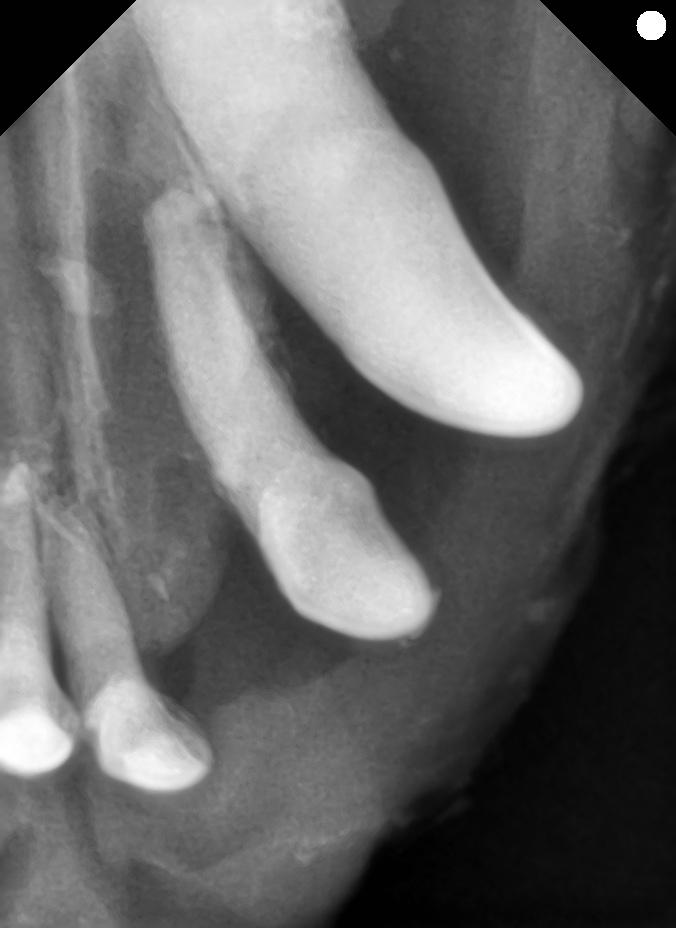

今回の症例は、16歳の高齢トイプードルです。

- 左上顎の切歯および犬歯に口腔鼻腔瘻を確認

- 歯周病の進行によって歯槽骨が大きく吸収されていました